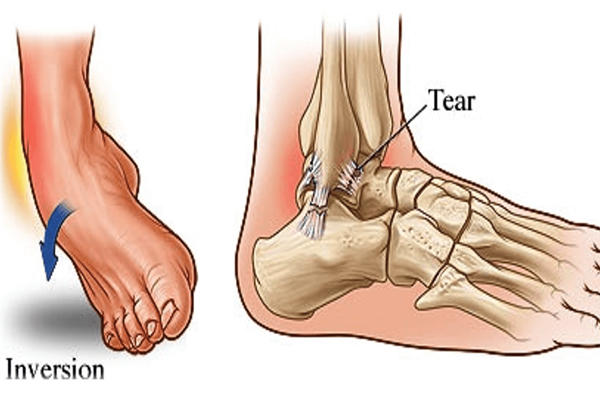

Ankle Sprain

“Had ankle twisting injury, managed well by doctor.. now pain-free and doing well.. highly recommended for your orthopaedic needs”